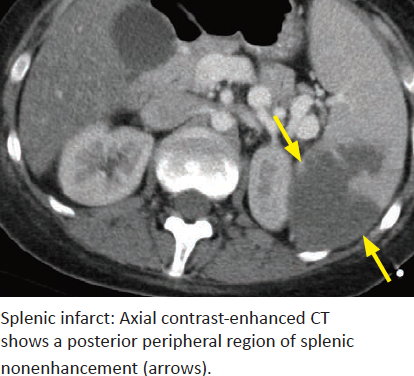

Splenic Infarcts

Cause in older patients vs younger patients?

Classical manifestation?

MR appearance?

Lack of enhancement of entire spleen should raise concern for what?